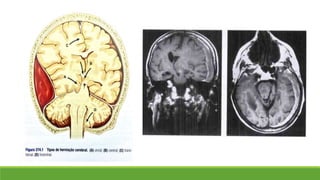

Lesões expansivas e herniações

A cavidade craniana é separada em compartimentos

 Dobras da dura-máter

 Foice do cérebro

 Tentório do cerebelo

Herniação: deslocamento do tecido cerebral para um espaço que normalmente não ocupa.

Coma e muitos dos seus sinais podem ser atribuídos a esses deslocamentos

Características clínicas podem ser típicas de herniações específicas → “localização falsa”